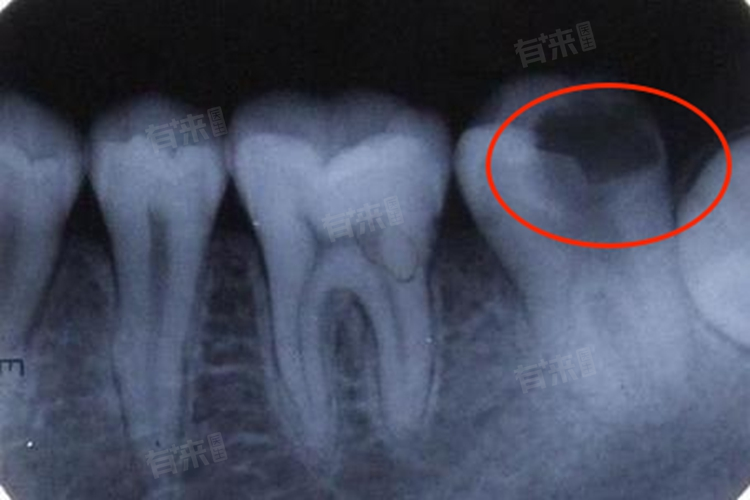

1、龋齿:口腔中的细菌分解食物残渣产生酸性物质,逐渐腐蚀牙齿,形成龋洞,严重时会导致牙齿部分缺失。如果龋坏程度较轻,可将龋坏组织去除干净,然后用补牙材料进行填充,恢复牙齿的外形和功能。若龋坏已累及牙髓,引起牙髓炎或根尖周炎,则需要先进行根管治疗,去除感染的牙髓组织,再进行补牙或做牙冠修复。